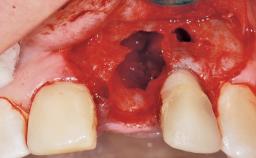

Late Flapless Placement of an Implant in a Maxillary Left Central Incisor Site

Anthony Sclar

A 39-year-old male patient presented with a chief complaint of discomfort and gingival discoloration around his maxillary left central incisor. He was in good general health and was a non-smoker. His past dental history was significant because of the traumatic fracture of tooth 21 in a sporting accident at age 13. Initial dental treatment included endodontic therapy and a full-coverage restoration. The patient became symptomatic 5 years later, when structural failure of the tooth resulted in the dislodgment of the crown. Endodontic retreatment, apical surgery, and post-and-core restoration were performed.

Bone Volume Deficient horizontally, requiring prior grafting